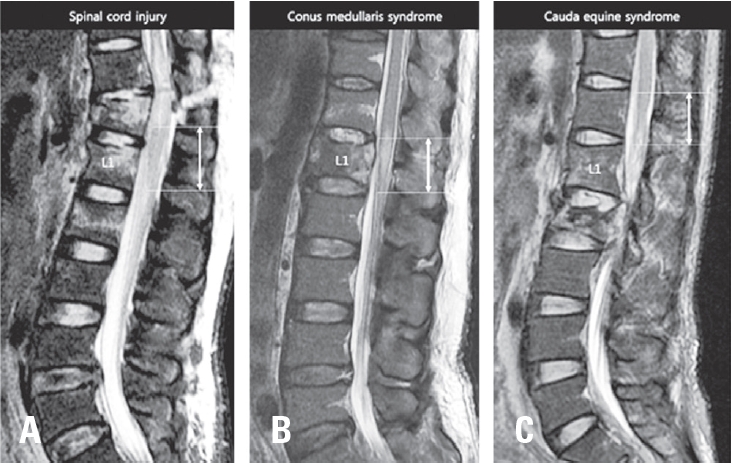

2. Radiological analysis

T2 weighted mid-sagittal MRI scans at acute injury were collected for each patient. MRI mid-sagittal image was defined as a sagittally oriented image in which the spinous processes were best visible. Three categories of intramedullary signal in CM were determined according to the presence of intramedullary edema or hemorrhage (Fig. 2). Type I is normal without signal change in CM. Type 2 is intramedullary edema in CM, which had intramedullary lesions of high signal intensity on T2-weighted image. Type 3 is mixed intramedullary edema and hemorrhage in CM. Intramedullary hemorrhage present with low signal intensity on T2-weighted image. Maximal vertical length of intramedullary edema in CM was measured on T2-weighted sagittal image. Maximal canal compromise at mid-sagittal image was determined by measuring anteroposterior (AP) canal diameter at the point of maximal canal compromise. Maximal AP canal encroachment ratio was calculated using AP canal diameters of fractured vertebra (DF) and one level above (DA) and below (DB) vertebra; maximal osseous canal compromise=[1-DF/{(DA+DB)/2}]×100%. All radiological measurements were done by one experienced surgeon who was blinded to neurological outcome of patients and done by picture archiving and communication system (INFINITT PACS; INFINITT, Seoul, Korea).

Fig. 2.

Signal characteristics in conus medullaris of MR image. (A) Type I: MR image of simple compression of conus medullaris without signal change in conus medullaris. (B) Type II: MR image of intramedullary edema in conus medullaris manifesting as T2 hyperintensity on conus medullaris (white arrow). (C) Type III: MR image of intramedullary edema and hemorrhage manifesting as T2 hypointensity (grey arrow) surrounded by T2 hyperintensity.

Signal changes in SCI are considered as the important predictor of neurologic recovery.16) Cord edema is seen on T2 MRI sequences as a hyperintensity of the signal within the cord and intramedullary hemorrhage manifests as T2 hypointensity within the cord.9,10,16,28,29) Hemorrhage is almost always present concurrently with edema, and on an MRI it is surrounded by a hyperintensity normally associated with edema. Intramedullary hemorrhage on T2W imaging is universally associated with some component of irreversible injury and arguably the most robust MR imaging predictor of injury severity.9,12,13,16) There is insufficient evidence to support other individual MR imaging features, including cord edema, swelling, and lesion length, for predicting neurologic outcomes in SCI.16) CM is most caudal part of spinal cord. Therefore we applied this prognostic method on T-CMS. Signal characteristics of MRI in spinal cord were also present in CM of T-CMS patients. Although signal characteristics and length of edema were significantly different between bladder function groups, the presence of intramedullary hemorrhage in CM was the only prognostic factor of bladder dysfunction in multivariate logistic regression model in T-CMS as found in studies of SCI.